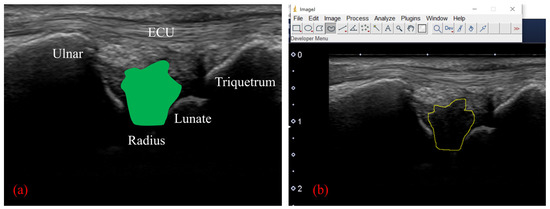

Motion Analysis of the Extensor Carpi Ulnaris in Triangular Fibrocartilage Complex Injury Using Ultrasonography Images

by Shuya Tanaka, Atsuyuki Inui, Yutaka Mifune, Hanako Nishimoto, Tomoya Yoshikawa, Issei Shinohara, Takahiro Furukawa, Tatsuo Kato, Masaya Kusunose and Ryosuke Kuroda

Sensors 2022, 22(21), 8216; https://doi.org/10.3390/s22218216 - 27 Oct 2022

The subsheath of the extensor carpi ulnaris (ECU) tendon, a component of the triangular fibrocartilage complex (TFCC), is particularly important as it dynamically stabilizes the distal radioulnar joint. However, the relationship between TFCC injury and ECU dynamics remains unclear. This study aimed to [...] Read more.

The subsheath of the extensor carpi ulnaris (ECU) tendon, a component of the triangular fibrocartilage complex (TFCC), is particularly important as it dynamically stabilizes the distal radioulnar joint. However, the relationship between TFCC injury and ECU dynamics remains unclear. This study aimed to analyze ECU movement and morphology using ultrasonography (US) images. Twenty wrists of patients with TFCC injury, who underwent TFCC repair, were included in the injury group, and 20 wrists of healthy volunteers were in the control group. For static image analysis, curvature and linearity ratios of the ECU in US long-axis images captured during radioulnar deviation were analyzed. For dynamic analysis of the ECU, the wrist was moved from radial deviation to ulnar deviation at a constant speed, and the velocity of the tendon was analyzed using particle image velocimetry. The static analysis showed that the ECU tendon was more curved in ulnar deviation in the injury group than in the control group, and the dynamic analysis showed that only vertical velocity toward the deep side during ulnar deviation was higher in the injury group. These results suggest that TFCC injury caused ECU curvature during ulnar deviation and increased the vertical velocity of the ECU during wrist deviation. Full article